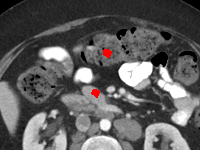

Visual comparison. As shown in Fig. 5, metallic implants such as spinal rods and hip prosthesis cause severe streaky artifacts and metal shadows, which obscure bone structures around them. cGan-CT cannot recover image intensity correctly for both cases. Sinogram domain or dual-domain methods perform much better than cGan-CT. LI, NMAR, and CNNMAR introduce strong secondary artifacts and distort the whole images. In NMAR images, there are fake bone structures around the metals, which is related to segmentation error in the prior image from strong metal artifacts. The segmentation error is also visible in NMAR sinogram. CNNMAR cannot restore the correct bone structures between rods in case 1. The tissues around the metals are over-smoothed in DuDoNet because LI sinogram and image are used as inputs, and the missing information cannot be inferred later. Our model retains more structural information than DuDoNet and generates anatomically more faithful artifact-reduced images.

Visual comparison. Fig. 7 shows two clinical CT images with metal artifacts. Case 1 is with moderate metal artifacts. cGan-CT does not suppress the artifacts completely and generates some fake details. LI, NMAR, CNN-MAR remove all the artifacts but introduce new streak artifacts, which is caused by the discontinuity in the corrected sinogram. DuDoNet outputs over-smoothed sinogram, which leads to blurred tissues close to the metal implants, such as muscle and bone. Only our model can provide realistic enhanced sinogram and remove the artifacts while retaining the structure of nearby tissues. Case 2 is very challenging as the rods bring strong metal shadows and bright artifacts around the vertebra. cGan-CT recovers the shape of vertebra but changes the overall image intensity. Other sinogram inpainting methods fail as the soft tissue and bone near the rods are heavily distorted. Our model removes part of the dark bands and reproduces correct anatomical structures around the rods.